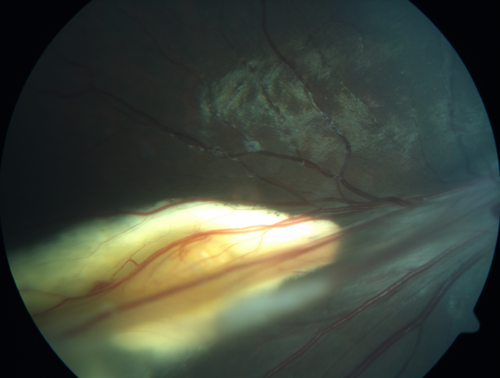

Familial Exudative Vitreoretinopathy - FEVR - Stage 4b OD

10 year old child with poor vision OD from birth.  The left eye had vascular remodelling in the temporal periphery with preretinal abnormalitlies seen on OCT.  The patient never returned for a fluorescein angiogram.  Left eye is either stage 1 or stage 2. no family history